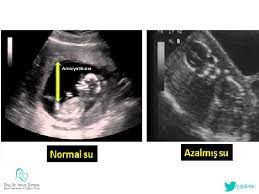

asagidaki ultrason resminde gordugunuz gibi bebegin etrafindaki siyah renkli kisim suyudur buna amniyotik sivi diyoruz bizler icin hava neys olum beyin hasari